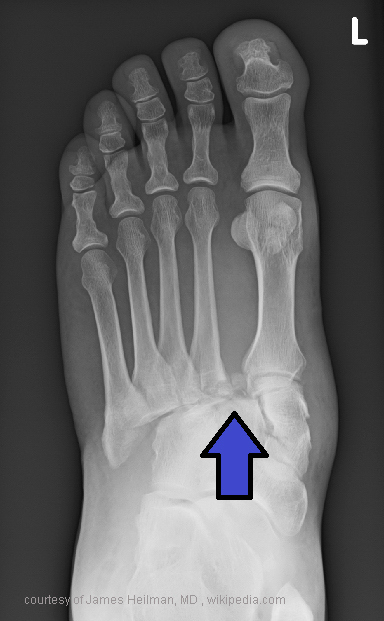

What is a Jones fracture?

Transverse fracture 2 cm from base of 5th metatarsal.

What causes avulsion fracture of 5th metatarsal?

Peroneus brevis pulling during inversion.

Common cause of avulsion fracture of 5th metatarsal?

Dance injury or awkward step.

Treatment for avulsion of 5th metatarsal?

4–6 week cast, usually heals well.